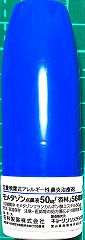

22.10.29 鼻炎薬吸引 モメタゾン点鼻液50μg 噴霧用 5mg10g 杏林 56噴霧用